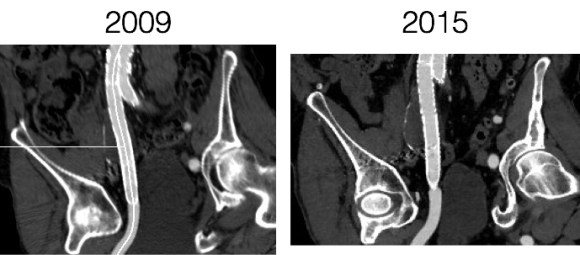

For example, take this patient who after EVAR of aortic aneurysm with AFX developed metachronous dilatation of the common iliac artery to 3.9cm with abdominal pain. The average diameter is 18.5mm. From the table, that rounds to 19mm corresponding to 283.53 square mm. If the internal iliac artery requires a 13mm graft, that is 132.73 square mm, the difference being 150.80 square mm. That corresponds to a 14mm diameter graft, but a slightly larger graft is preferred for oversizing. The external iliac artery is 8mm, and putting a 13mm Viabahn (largest available) in that would result in the B-infolding in the 8mm external iliac. Here, I bailed myself out by simply placing a 20mm AFX iliac limb extension, which by virtue of its design is resistent to infolding and tolerant of parallel grafts laid alongside in constricted channels. I found that the AFX iliac limb, a 20-13mm x 88mm length extension well suited for this.

The AFX graft limb seems to adapt to the presence of the parallel “sandwich” graft which is deployed second and ballooned last. In followup, there was shrinkage of the common iliac artery aneurysm sac and no endoleak.

Compared to my other parallel graft case treating a metachronous saccular common iliac aneurysm years after an EVAR with a Gore endograft (link), which by table calculation, resulted in 8% oversize in calculated areas, this particular technique with a large AFX graft and an appropriately sized Viabahn seemed to work well the setting of a previously placed AFX graft. It allows one to avoid hypogastric occlusion.